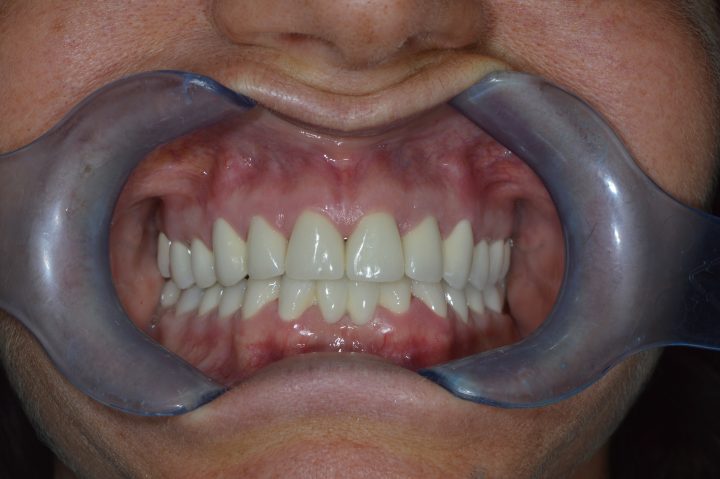

Daniel ist ein 54-jähriger Lastwagenfahrer. Seit seiner Kindheit hatte er schlechte Zähne, bis er in die Klinik kam, alle fallen raus.

Aufgrund von der CT- Aufnahme haben wir mit dem Patienten zusammen entschieden, dass wir 4-4 Alpha Bio Implantate in Ober- und Unterkiefer einsetzen.

Die Operation dauert zweimal 1,5 Stunden lang, und wurde der provisorische Zahnersatz im Ablauf den 5 Tagen fertig. Nach der 3 Monate langen Heilungszeit wurden zwei Stegprothesen auf 4-4 Implantate befestigt.

Die Implantatprothese sichert die Stabilität für den Patienten, so konnte Daniel am Ende der Behandlung wieder Steak essen, was sein Traum war.